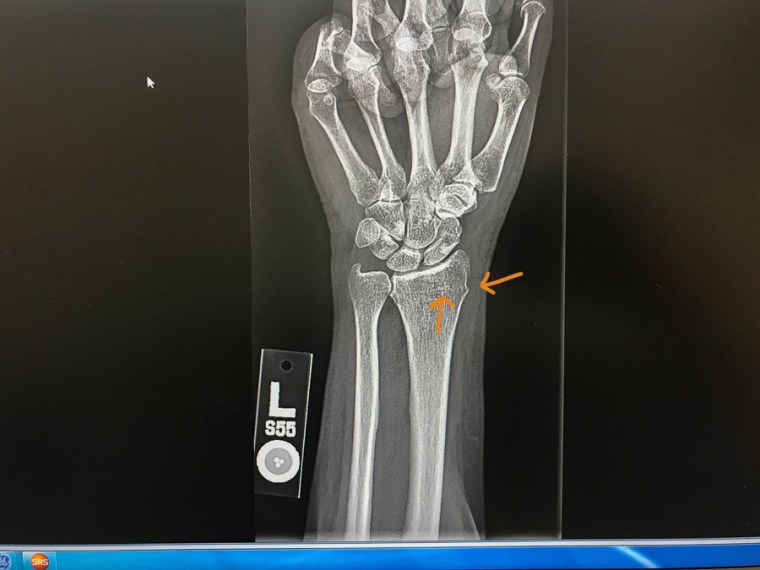

My xray. The fracture is the horizontal white line right above the arrow on the bone. You can also see that the bone buckled a little bit on the side with the piece pointing out.